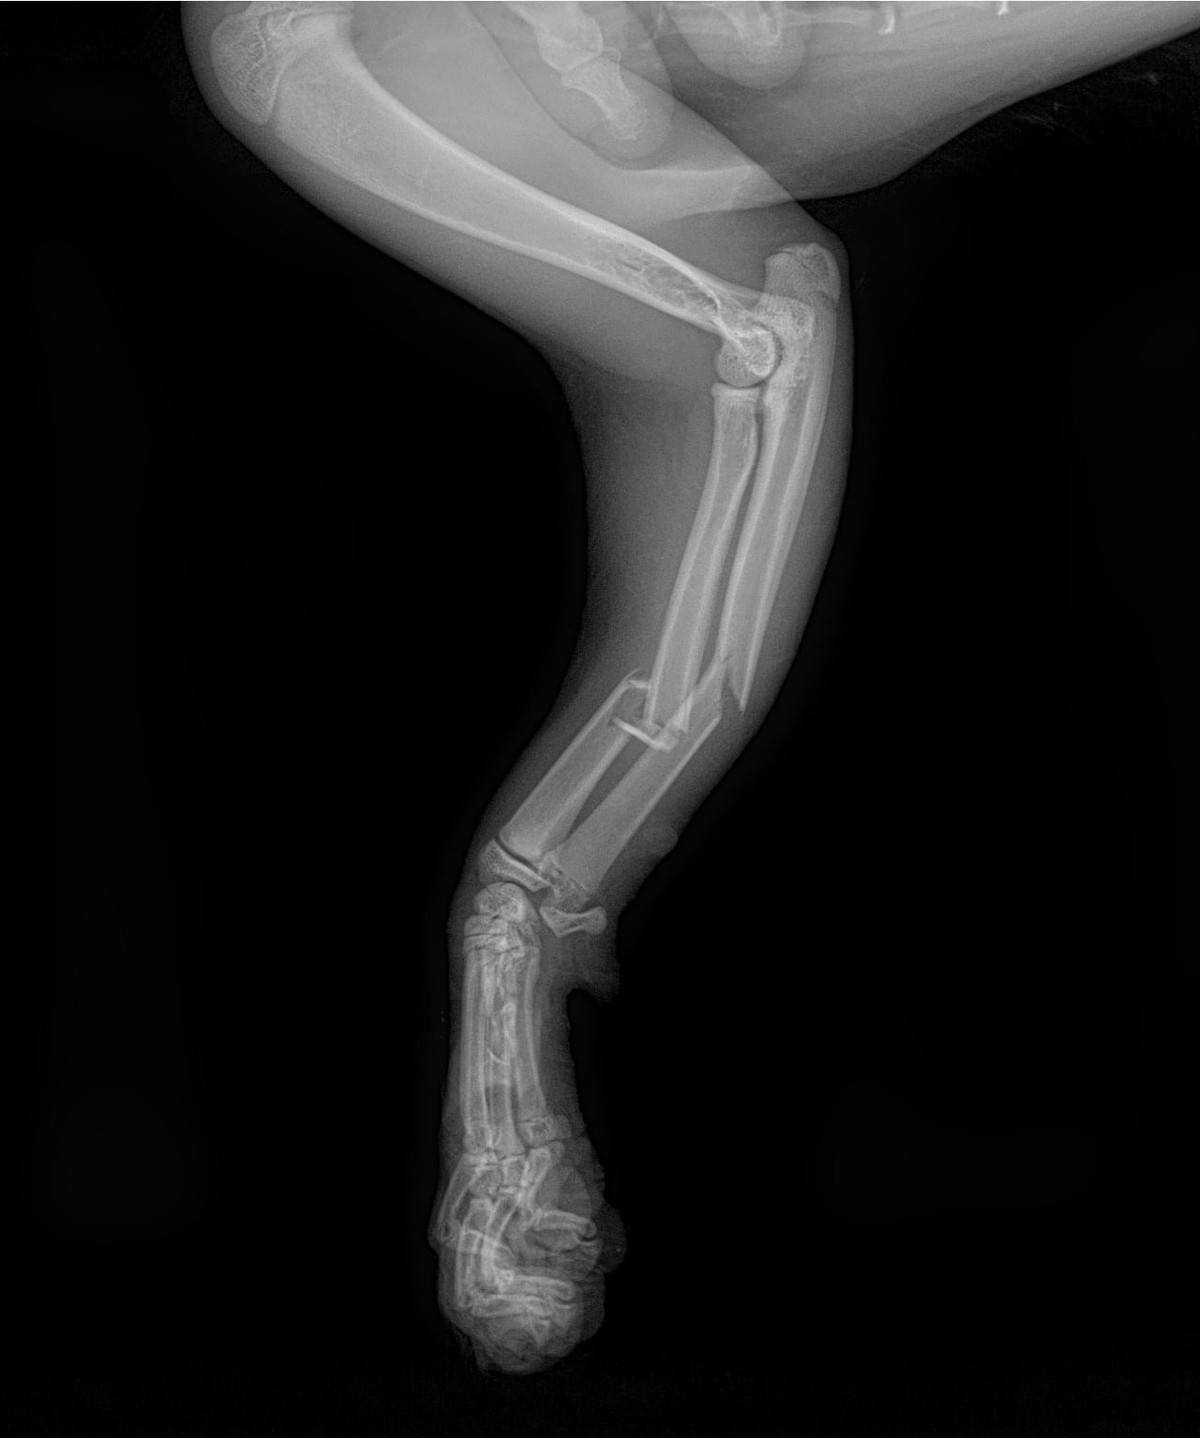

VEC的骨科服務建基於先進的醫療技術與緊密的團隊合作。中心採用國際認可的SecurosTM骨科用品,提供高品質的骨板、骨釘及外固定選項,以應對各類骨折修復與關節穩定手術。手術前,獸醫團隊會利用電腦斷層掃描獲取詳盡的立體影像,為制定精準的手術計劃提供關鍵資訊。

VEC每年處理過百次骨科及軟組織手術,常見病例包括小型犬的骨折修復及膝關節異位矯正。Dr. Hannah指出 :「在VEC,骨科病人會得到深切治療部及住院團隊的全面支援。手術前,他們能幫助危殆的動物穩定情況 ; 手術後,,提供密切的監測與護理,確保即使是最複雜的病例,在整個治療過程中都能得到最安全的管理。」

「我處理過其中一個難忘的病例,是一隻由高處墮下的貓咪(Tun Tun)送抵急症室時情況危殆,伴隨內出血及多處骨折。在ICU團隊的深切治療下,Tun Tun奇蹟般地穩定下來並成功接受了骨折修復手術。VEC跨團隊的無縫合作,是牠最終能康復成一隻活潑貓咪的關鍵。」Dr. Hannah分享道。與此同時,VEC亦有提供上門診症服務,讓寵物安在家中同時獲得醫療服務,跟進康復情況。